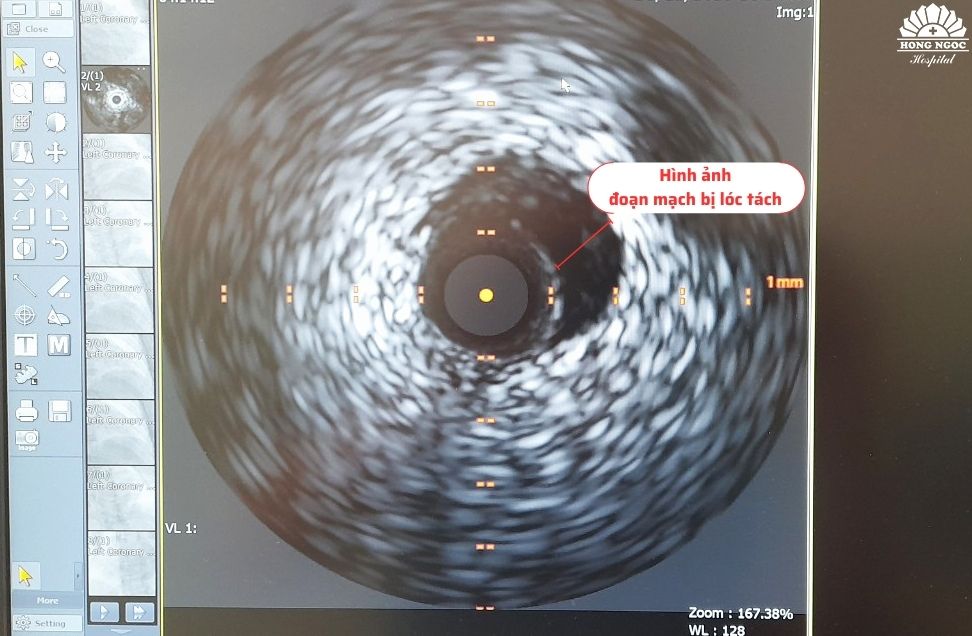

Đáng chú ý, trước đó sức khỏe bệnh nhân hoàn toàn bình thường, không có tiền sử bệnh tim mạch nhưng khi nhập viện, các triệu chứng lâm sàng lại hết sức nghiêm trọng, men tim tăng cao, ở mức 2816ng/L nên được chỉ định chụp mạch vành kết hợp siêu âm trong lòng mạch IVUS. Kết quả chụp cho thấy bệnh nhân bị nhồi máu cơ tim cấp do lóc tách đoạn 2 - 3 động mạch liên thất trước.

ThS.BS Nguyễn Đình Công, bác sĩ trung tâm Can thiệp tim mạch Hồng Ngọc, cũng là người trực tiếp can thiệp cho bệnh nhân Hà chia sẻ: “Hầu hết các trường hợp bị nhồi máu cơ tim cấp đều do huyết khối hoặc các mảng xơ vữa gây hẹp mạch vành… Tuy nhiên, với những trường hợp không có tiền sử bệnh như cô Hà, kèm theo các triệu chứng lâm sàng nghiêm trọng thì việc sử dụng kỹ thuật siêu âm trong lòng mạch là vô cùng cần thiết. Kỹ thuật này giúp chẩn đoán chính xác bệnh nhân bị hẹp hay lóc tách động mạch vành. Nếu chỉ chụp mạch vành số hóa xóa nền, hình ảnh hiển thị lòng thật và lòng giả rất khó phân biệt nên cần phải sử dụng IVUS vì kỹ thuật này thể hiện rõ được ba lớp cấu trúc của thành động mạch vành.”